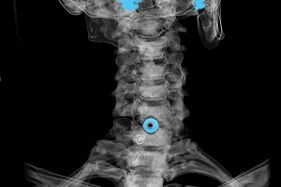

Диагнозата се установява въз основа на характерни симптоми, както и с помощта на:

- рентгенови лъчи. Методът е неефективен, особено в последните стадии на развитие на остеохондроза.

- MRI (магнитен резонанс) на шийните прешлени. Метод, който ви позволява да видите костни структури, херния на междупрешленните дискове, техния размер и посока на развитие.

- Компютърна томография. По-малко ефективно решение от MRI, тъй като наличието и размерът на хернията е трудно да се определи.